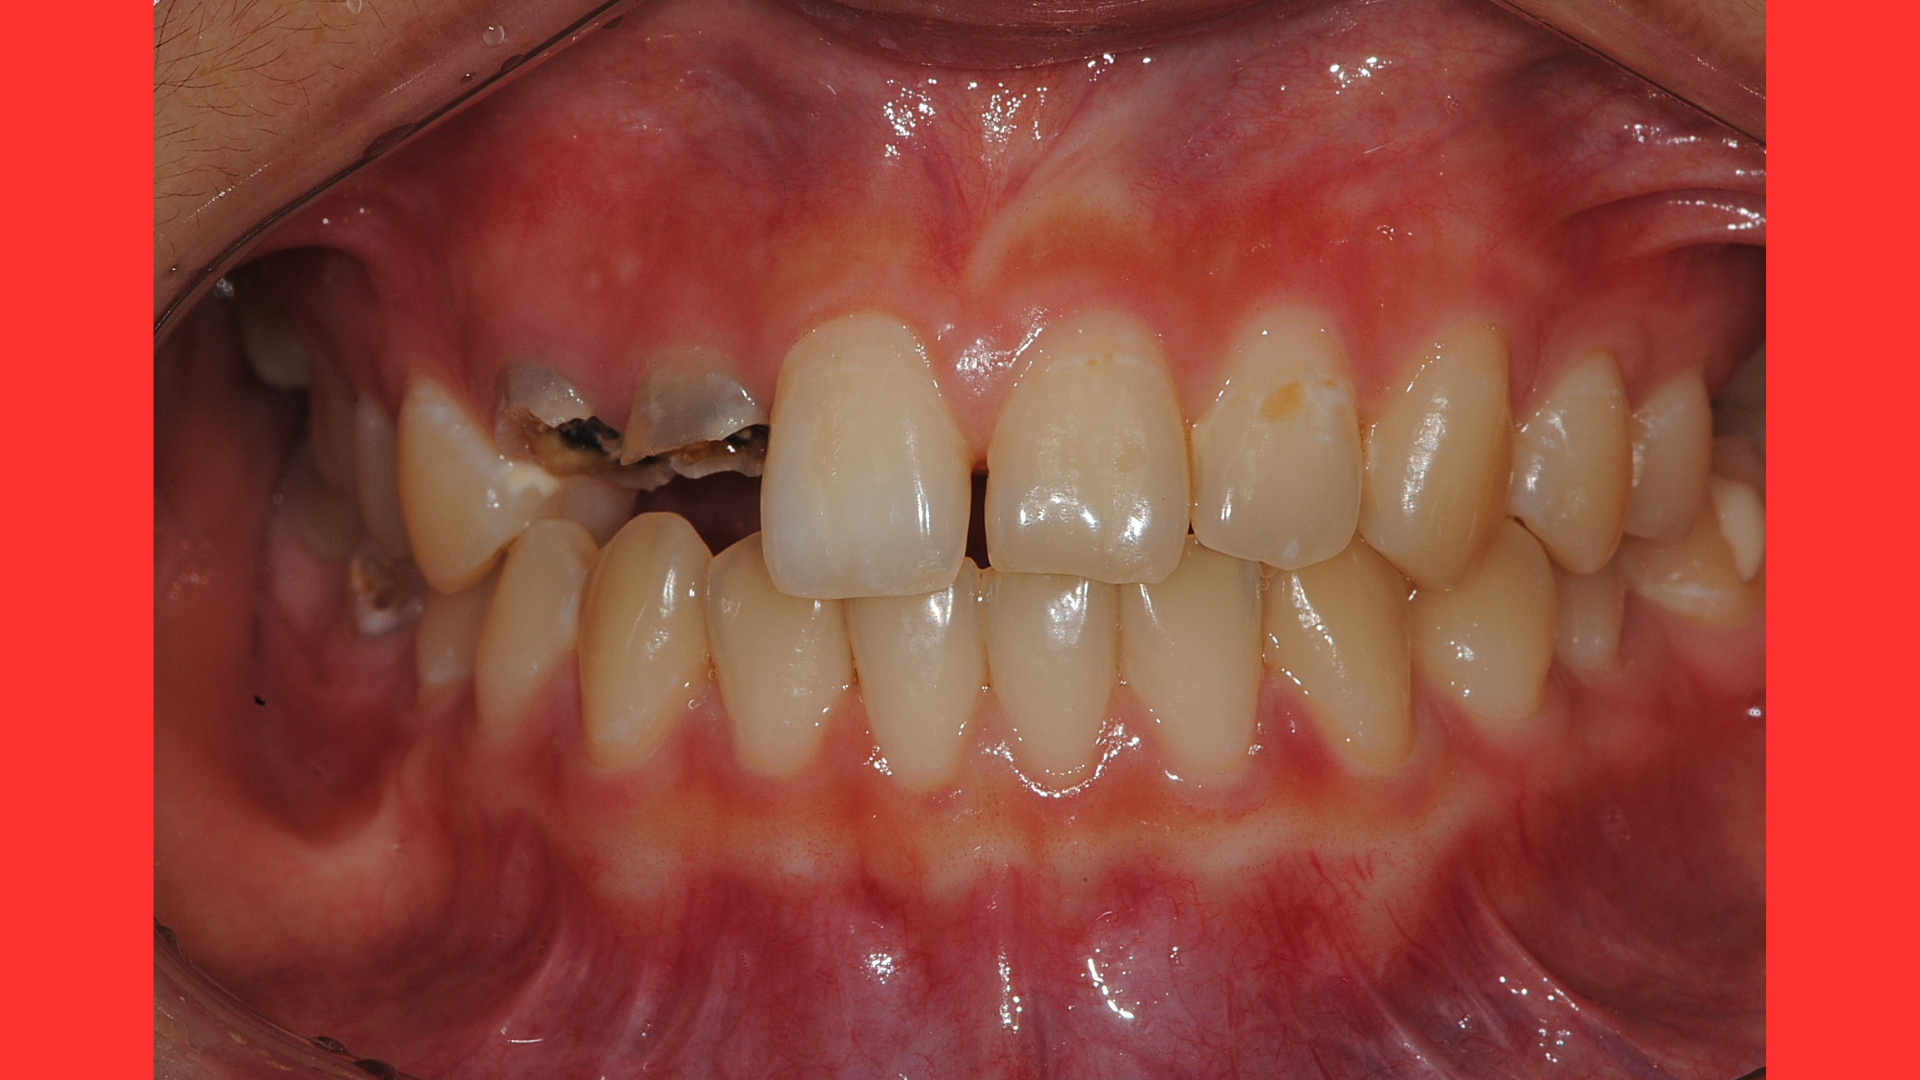

자.. 위사진을 보시죠... 치아2개가 충치가 심합니다.

잘보시면 까만색이 얼마나 깊이까지 있는지 생각을 해보도록 하죠.

잇몸밑까지 까만색이 비춰보이는 걸 알수 있겠죠?

즉 잇몸아래의 치아부분까지 썩은 것입니다.

이걸 뽑아야 할까요 살려야 할까요?

20대 초반의 여성환자분은데 뽑고 임플란트를 해야 할까요?

더군다나 앞니를 뽑는건 신중해야 합니다.

임플란트보철이 심미성을 고려한다면 최선의 선택이 될 수 없기 때문입니다.

가능하면 치아를 살려야 하는 것이 최우선으로 진행이 되어야 하는 부분입니다.